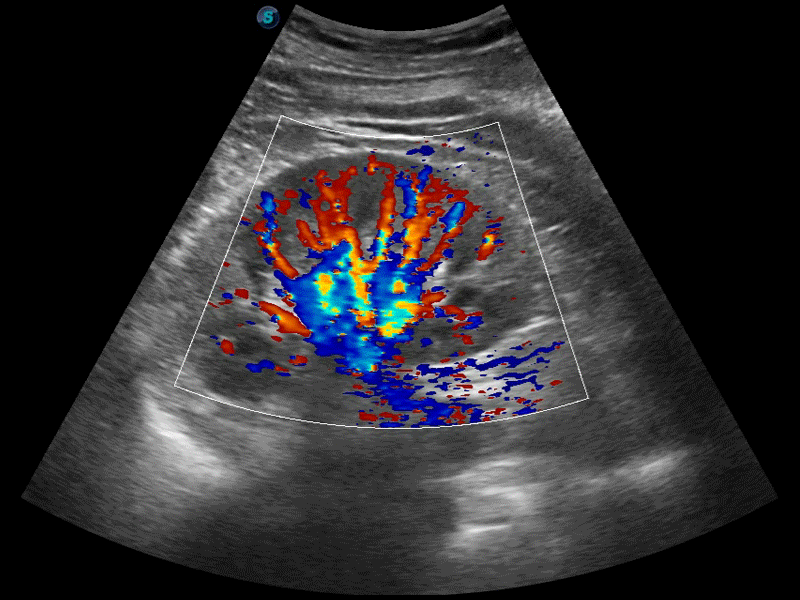

高分辨率血流成像技術(shù)提高了對(duì)低速血流信號(hào)的檢測(cè)能力。在提高空間分辨率的同時(shí),也克服了血流外溢現(xiàn)象,為用戶提供更加真實(shí)的血流動(dòng)力學(xué)信息。

凸陣、線陣和相控陣探頭進(jìn)行實(shí)時(shí)掃描時(shí),開啟擴(kuò)展成像模式,可以擴(kuò)展超聲圖像視野,以便更完整地查看大的病灶或組織器官的解剖結(jié)構(gòu)。

通過色彩血流和實(shí)時(shí)寬景相結(jié)合,可觀察到完整的靜脈或動(dòng)脈的血流,方便醫(yī)生檢查。實(shí)時(shí)掃查過程中,如有任何操作失誤也可以很容易地進(jìn)行回掃擦除,而不會(huì)中斷掃查。